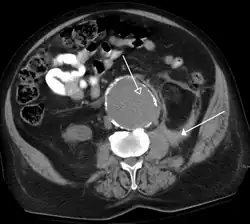

An axial contrast-enhanced CT scan demonstrating an abdominal aortic aneurysm of 4.8 by 3.8 cm -

Abdominal aortic aneurysms (3.4 cm)

An aortic aneurysm as seen on CT with a small area of remaining blood flow -